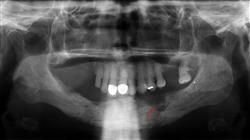

A incidência de Infecções Osteoarticulares na infância é alta, podendo ocorrer frequentemente em pacientes menores de 5 anos. Embora na maioria dos casos sejam crianças previamente saudáveis, há uma série de fatores que predispõem ao seu desenvolvimento. Sua etiologia é predominantemente bacteriana e existem certos achados clínicos que fornecem indícios para o diagnóstico.

Identificar adequadamente esses sinais e sintomas permite estabelecer uma terapia adequada às necessidades do paciente de forma precoce, para evitar sequelas ou complicações. Nos últimos anos, tem sido demonstrado que o uso de certas estratégias farmacológicas contribui para a melhoria dos sinais detectados. Por essa razão, o estudo de todos esses aspectos, desde as características microbiológicas das diferentes patologias infecciosas musculoesqueléticas em pacientes pediátricos até o manejo de outras artropatias não infecciosas, será abordado neste programa.

Este Curso Universitário abrange o conteúdo mais completo do cenário pedagógico atual, visando tratar de forma inovadora os conceitos que capacitam o especialista a realizar uma prática clínica avançada diária. O profissional aprenderá a manejar urgências em pacientes pediátricos com patologia infecciosa musculoesquelética e desenvolverá uma estratégia adequada no diagnóstico diferencial das doenças infecciosas e não infecciosas na Ortopedia Pediátrica.